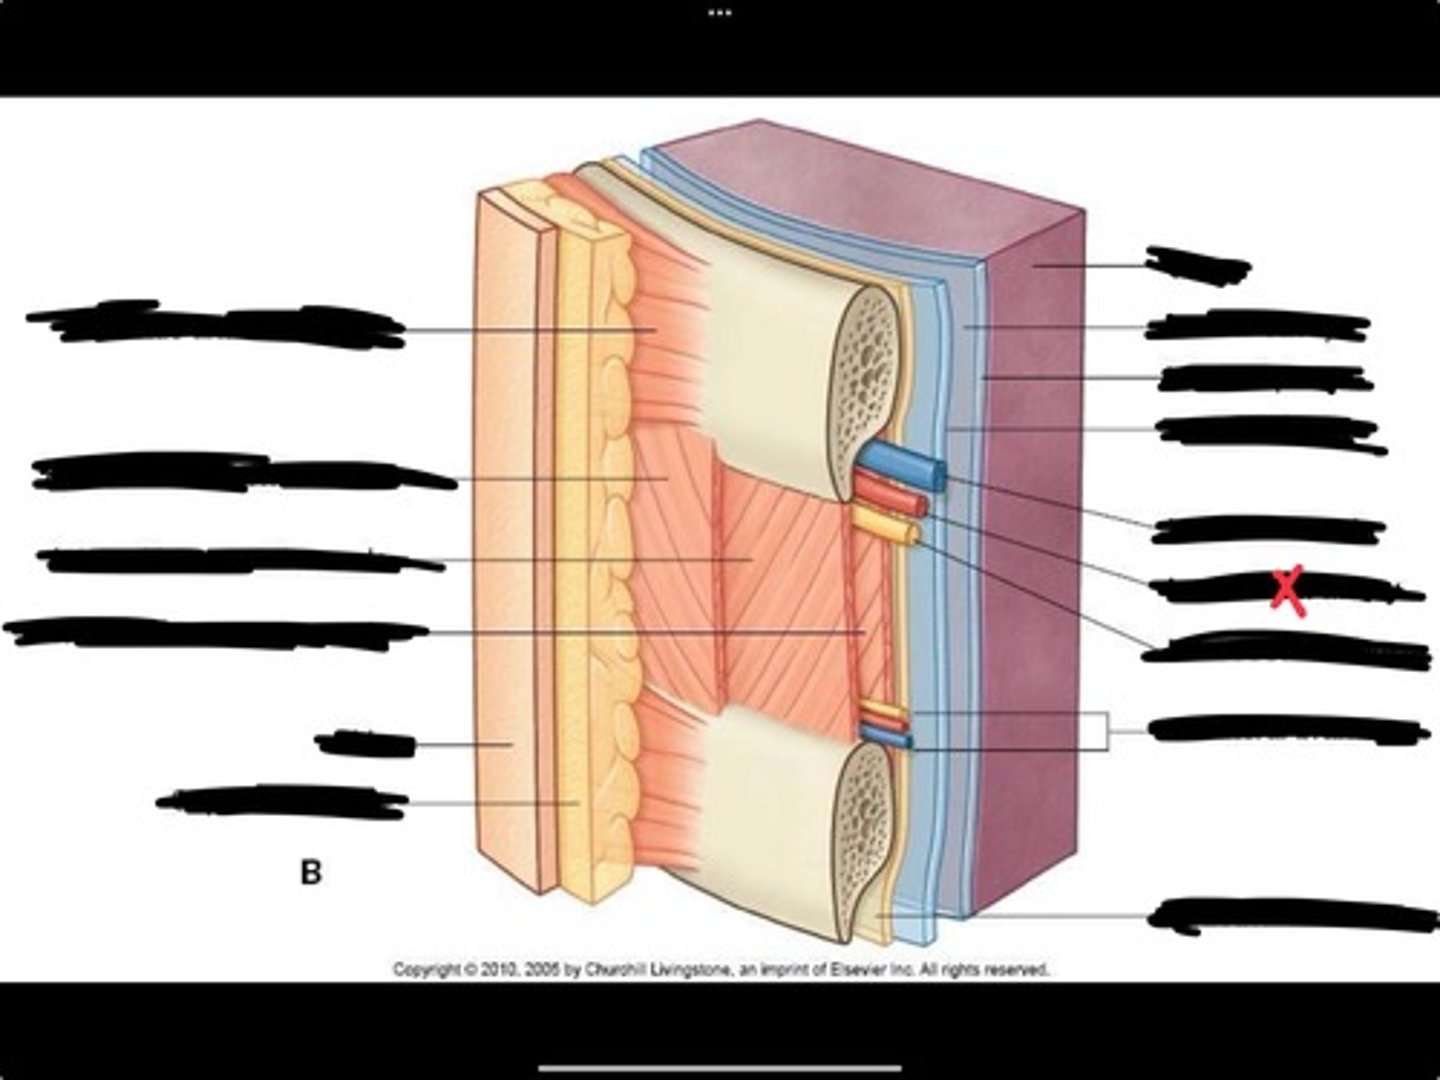

Innermost intercostal muscle

Skin

Internal intercostal muscle

External intercostal muscle

Serratus anterior muscle

Lung

Pleural cavity

Visceral pleura

Parietal cavity

Intercostal vein

Intercostal artery

Collateral branches

Intercostal nerve

Endothoracic fascia